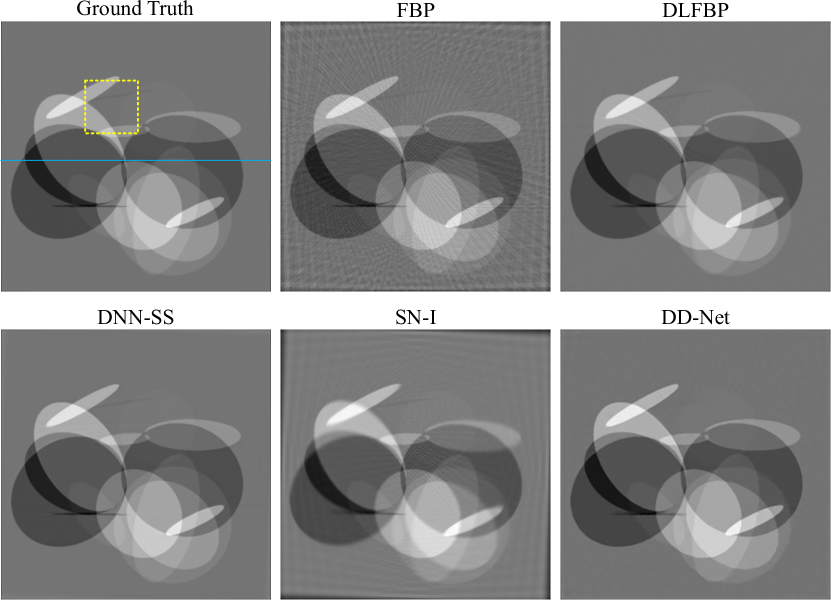

III-E2 Experimental data sets

Figs.8-Fig.10 present results of one of the 100 experimental abdominal slice with 120 views for testing using different methods. Same regions indicated with yellow box are enlarged for better visualization in Fig.9. The image intensity profile in same position is shown in Fig.10.

Still, SN-I could not completely remove the artifacts, and its edge is blurred. As shown in Fig.9 and Fig.10, DLFBP, DNN-SS and DD-Net could suppress the artifacts clearly, while the result from DD-Net is overly smoothed and loses details.

Refer to caption

Figure 8: One group of results from experimental data sets with incomplete phase-contrast sinogram of 120 views, using FBP, DLFBP, DNN-SS, SN-I and DD-Net. Same regions of these images, indicated by yellow box, are enlarged for better visualization.

Figure 9: Enlarged regions indicated by yellow box in Fig.8 for better visualization. DLFBP and DNN-SS could remove the artifacts and keep tiny structures.